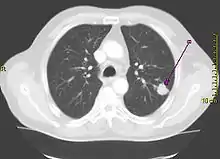

Солитарный лёгочный узел (одиночное периферическое образование) — в рентгенологии, периферическое образование в лёгочной ткани размером менее 3 см. Может быть случайной находкой на 0,2 % рентгенограмм грудной клетки[1] и около 1 % компьютерных томограмм[2].

Рентгенограмма грудной клетки, демонстрирующая солитарный лёгочный узел в верхней доле левого лёгкого. | |

| Вид исследования | Рентгенография, компьютерная томография, позитронно-эмиссионная томография |

| Область исследования | Грудная клетка |